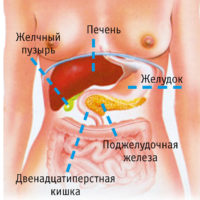

A hasnyálmirigy egy fontos része az emésztőrendszer. Ez felelős a hormonok és enzimek, amelyek szabályozzák az emésztést és a tápanyagok beépülését. Gátlása szervi funkciók vezet hibás működését az emésztőrendszer, nagy valószínűséggel a fejlődő megbetegedések.

Mi az a struktúra, és ahol a hasnyálmirigy emberben

Mi a szerkezet az emberi emésztőrendszer